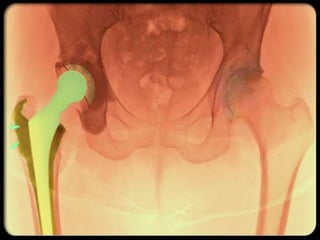

INDICATIONS OF SURGICAL

INTERVENTION

• Severe joint pain,

resistant to conservative treatment

methods

• Limitation of daily living activities

• Deformity, angular deviations, instability

INVASIVE METHODS

Osteotomy

Joint replacement

INDICATIONS OF SURGICAL INTERVENTION •Severe joint pain, resistant to conservative treatment methods • Limitation of daily living activities • Deformity, angular deviations, instability

INVASIVE METHODS • Jointlavage • Arthroscopy • Cartilage grefting- genetic engineering • Surgery Osteotomy Joint replacement